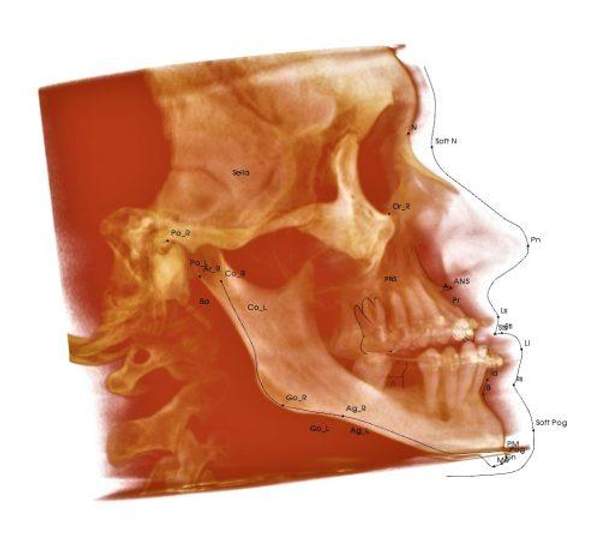

Цефалометрический анализ

3D-цефалометрия (Dolphin) (результат в течение 5 рабочих дней) = 3500р. Анализ и расчет ТРГ в прямой или боковой проекции в Dolphin  (результат в течение 3 рабочих дней / 1 рабочего дня) = 2350р. / 2900р. Сравнительный анализ и расчет ТРГ в Dolphin (сравнение до 4 расчетов снимков/ более 4 расчетов снимков) = 1000р. / 1500р.